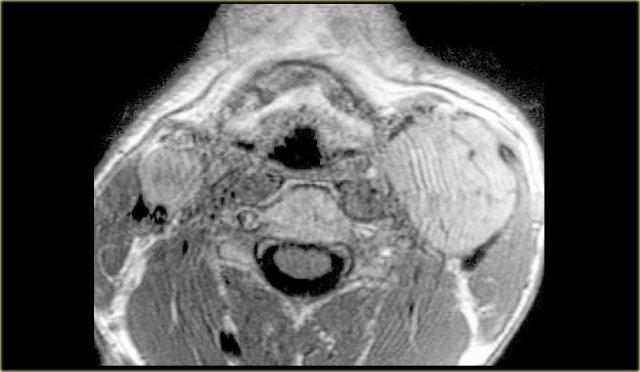

Paraganglioma: Hình ảnh MRI chuỗi xung T1W có tiêm thuốc tương phản từ Gadolinium tại mức thanh quản trên thanh môn

Paraganglioma

Bước 1: Xác định khoang

Bên trái là hình ảnh một bệnh nhân có khối sưng ở bên trái cổ.

Hãy quan sát hình ảnh MRI tại mức thanh quản trên thanh môn và xác định tổn thương nằm trong khoang nào.

Sau đó tiếp tục đọc.

Khối sưng nằm tập trung giữa động mạch cảnh ngoài và động mạch cảnh trong.

Lưu ý rằng các mạch máu này bị chèn ép.

Rõ ràng tổn thương này phải nằm trong khoang cảnh.

Cần lưu ý rằng có một tổn thương nhỏ hơn nhưng có hình thái tương tự, nằm ở khoang cảnh bên phải.

Paraganglioma thường gặp dạng đa ổ ở 3% đến 5% bệnh nhân nói chung và 20% đến 30% ở những người có tiền sử gia đình dương tính.

Các tổn thương này ngấm thuốc mạnh trên CT và MRI như được thấy trên hình ảnh MRI mặt phẳng coronal sau tiêm Gadolinium này.

Trong tổn thương lớn hơn ở bên trái, có thể thấy các vùng mất tín hiệu dòng chảy điển hình (xem thêm hình ảnh mặt cắt ngang).

Vì vậy, chúng ta có thể kết luận rằng có các tổn thương ngấm thuốc mạnh hai bên với hiện tượng mất tín hiệu dòng chảy trong khoang cảnh, nhiều khả năng nhất là u thể cảnh hoặc paraganglioma.